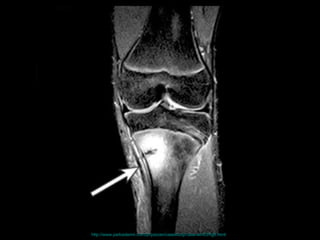

壓力性骨折 Stress Fracture 疲勞骨折 Fatigue fracture   骨質不良性骨折 Insufficiency fracture http://www.emedicine.com/radio/topic783.htm

http://www.gentili.net/images/200/stressfxkneeapx1600.jpg

http://www.parksidemri.com/physician/casestudy/case-win03/images/case7.jpg

http://www.parksidemri.com/physician/casestudy/case-win03/fig6.html